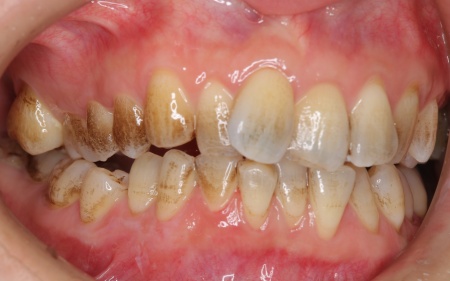

30代女性 デコボコした歯並びをワイヤー矯正とセラミック治療で改善した症例

拝見したところ、歯が全体的にずれたりねじれたりして生えており、歯並びがデコボコしていました。 また、数本の歯にはプラスチックの詰め物が装着されていましたが、経年的な劣化により歯との間に段差が生じています。これも噛み合わせのバランスを崩す原因のひとつになっていると考えられました。 歯並びや噛み合わせの乱れをこのまま放置すると、歯磨きがしにくくなり虫歯や歯周病のリスクが高まるほか、特定の歯に強い力がかかり続けることで将来的に歯の寿命に影響を及ぼすおそれもあります。

治療前